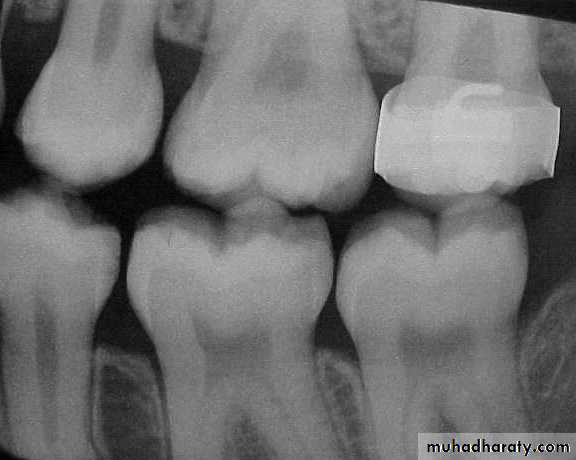

Bitewing radiograph. This radiograph shows (1) large occlusal caries, (2) radiolucent lines or mach band effect (an optical illusion caused by overlapped enamel), (3) interproximal caries, and

(4) cervical burnout